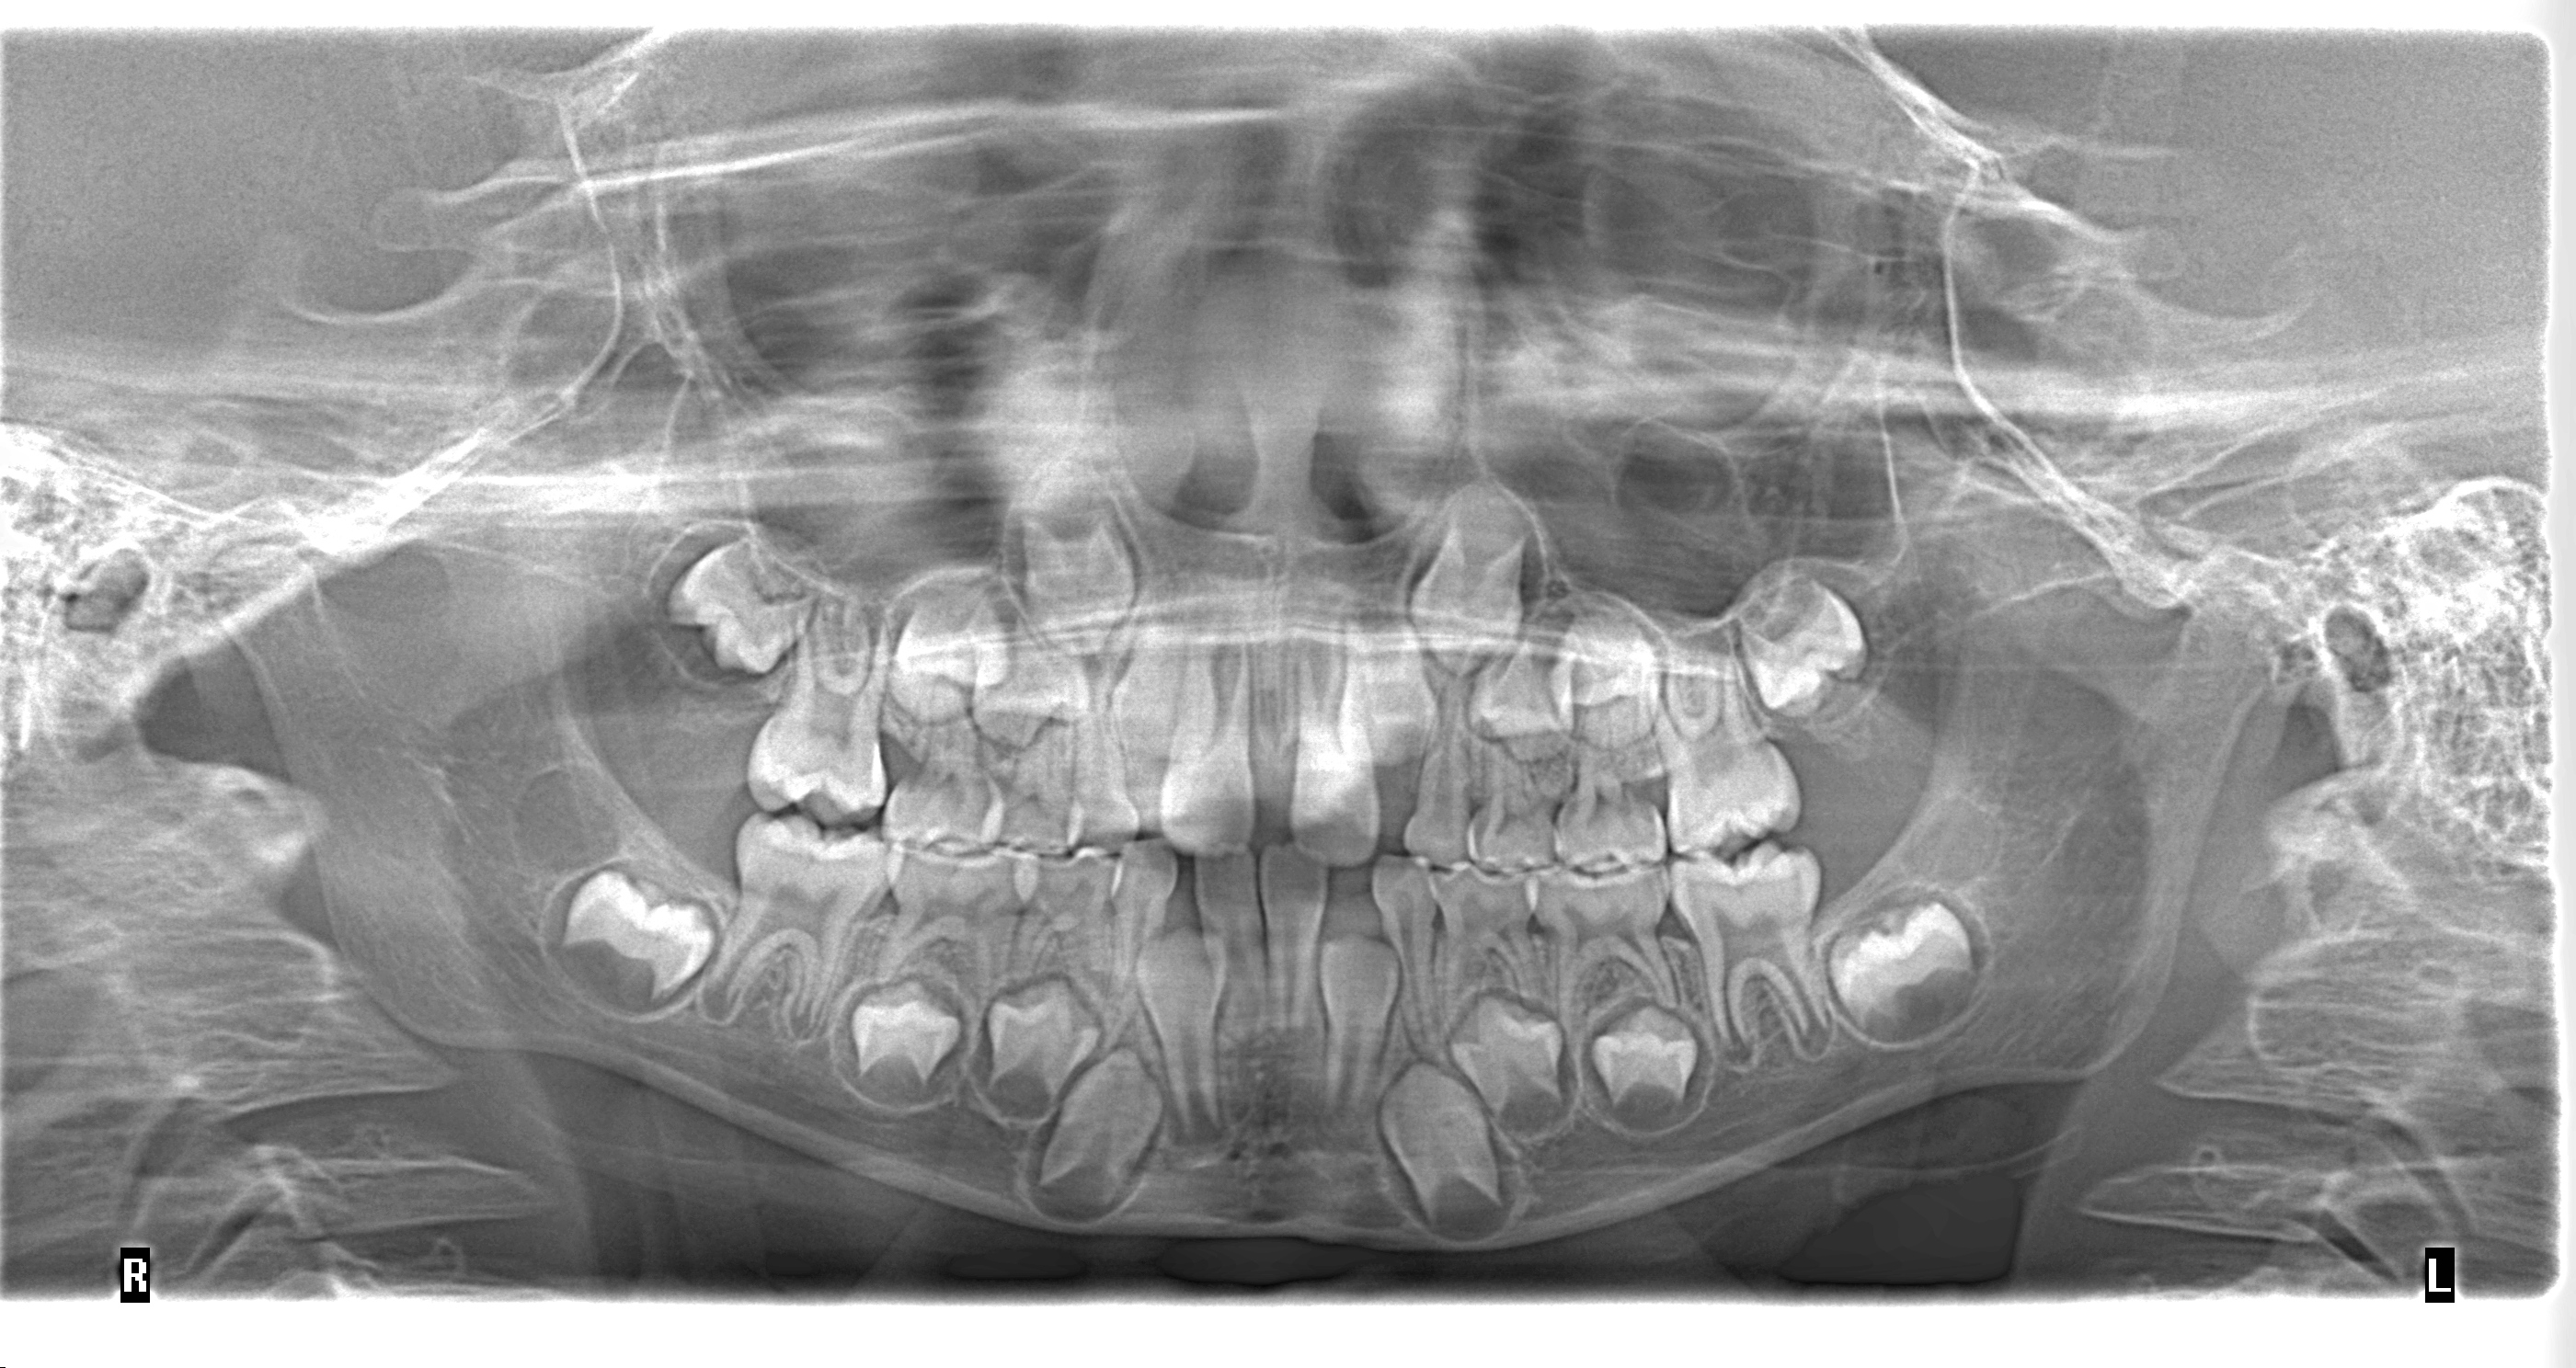

Tomografia Maxilar

Tomografia Bimaxilar, un maxilar o por zonas